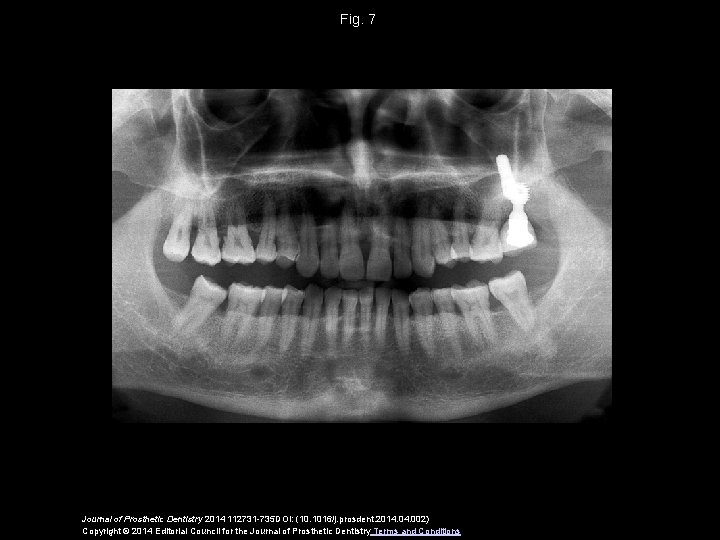

Fig. 7 Journal of Prosthetic Dentistry 2014 112731 -735 DOI: (10. 1016/j. prosdent. 2014. 002) Copyright © 2014 Editorial Council for the Journal of Prosthetic Dentistry Terms and Conditions